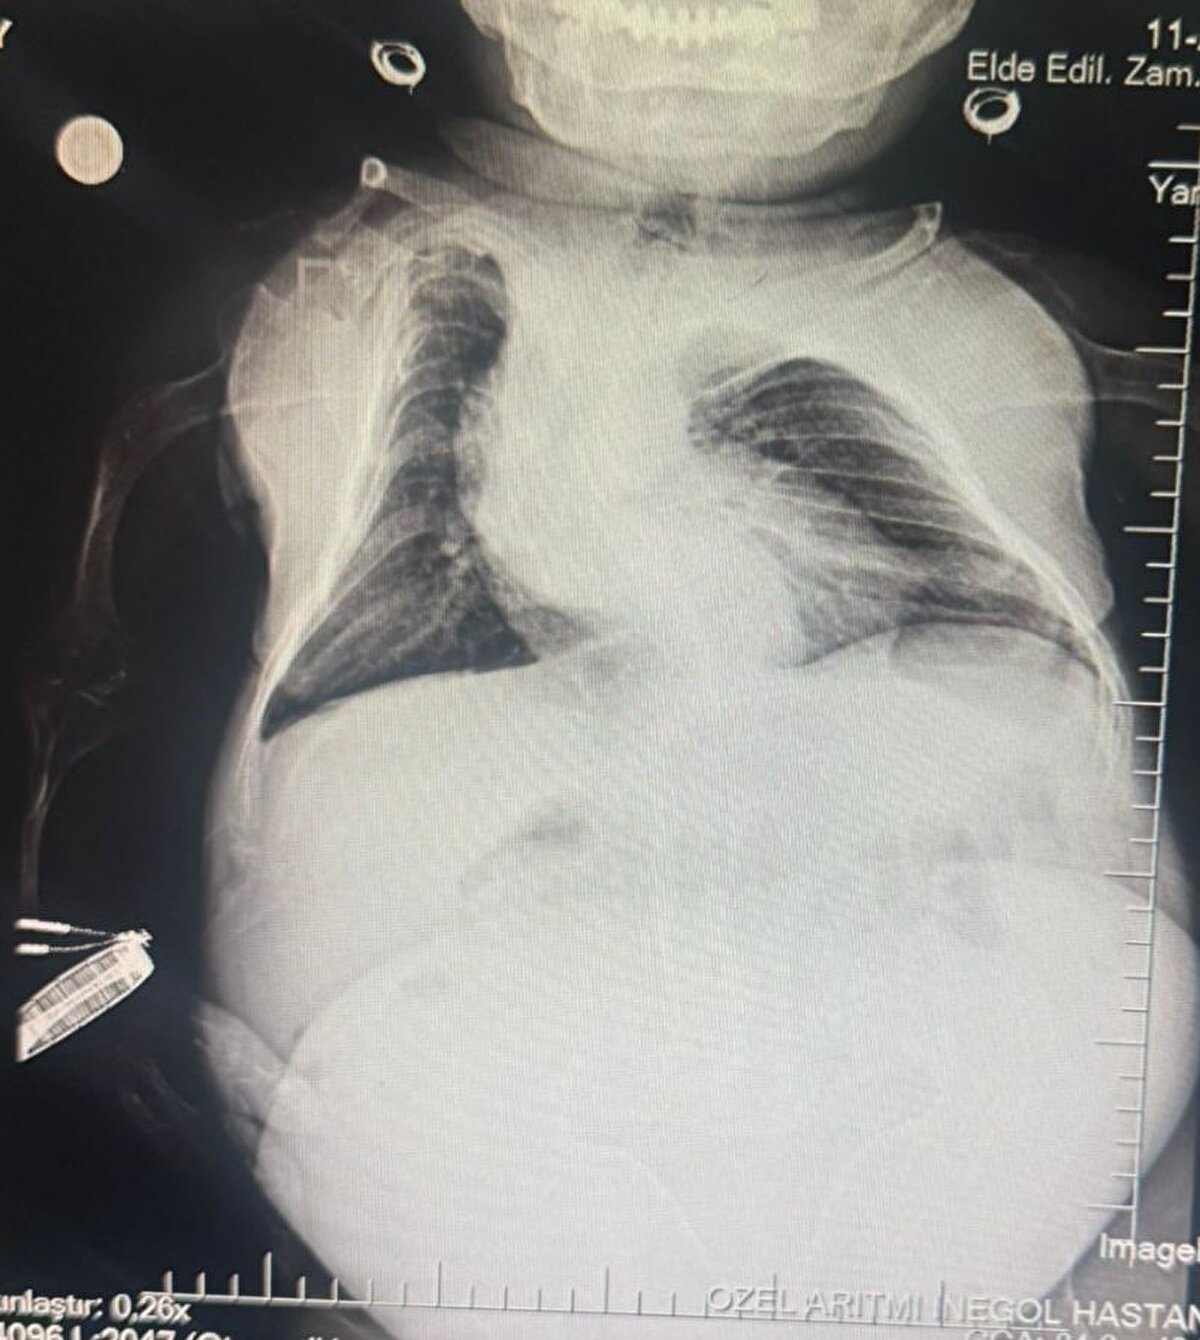

Halk arasında cücelik olarak bilinen Akondroplazi rahatsızlığı ile dünyaya gelen 30 yaşındaki Nurdan Tüfekçi, son 1 yıldır yaşadığı karın ağrısı şikayeti nedeniyle birçok hastaneye başvurarak tedavi gördü. Son olarak İnegöl’deki özel bir hastanenin kadın hastalıkları bölümüne başvuran 80 santim uzunluğunda ve 24 kilogram ağırlığındaki Nurdan Tüfekçi’nin yapılan tetkiklerinde yumurtalığında 3 kilogram kist olduğu tespit edildi.

Hasta hemen ameliyata alındı. Belinden yapılan anestezi ile uyanık şekilde 1.5 saat süren ameliyatı başarılı geçen Tüfekçi, 3 kilogram olan kistten kurtulması ile 24 kilogramdan 21 kiloya düştü.

Anestezi Doktoru Mahmut Gül, "Hastamız 30 yaşında. 80 santimetre boyunda, 24 kilo ağırlığında bir kardeşimiz. Kendisinin yumurtalıklarında kist olduğu için ameliyat olması gerekti. Biz bu ameliyatta hastamıza önce büyük bir damar yolu açtık kasıktan. Çünkü damar yolunun çok önemi var ve daha sonrasında ameliyat sırasında belinden uyuşturduk ve ameliyatı sorunsuz bir şekilde belden uyuşturmayla hastamız uyanık bir şekilde tamamladık. Hastadan 3 kilo kist çıktı. Öncesinde 24 kilo olan hastamız, ameliyat sonrasında 21 kiloyla şifalı bir şekilde serviste yatıyor. Ameliyatı bugün oldu. Şu anda da serviste hastamız. Bu tür ameliyatlarda uyutmak hastamız açısından oldukça risklidir. Biz o yüzden bölgesel anesteziyi yani belden uyuşturmayı tercih ettik. Literatürde çok olmayan bir hasta ve güvenli bir şekilde hastanemizde bu ameliyat tamamlandı" dedi.

Kadın Hastalıkları Uzmanı Mustafa Kır, "Hastamızda 20 santimlik tümör vardı kistlik yapıda. Onu başarılı bir operasyonla çıkarttık" şeklinde konuştu.